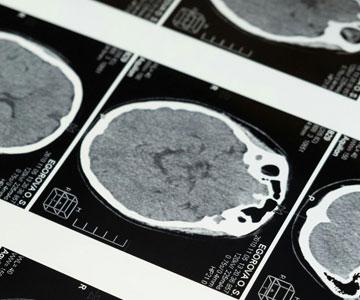

The Early Years of Brain Imaging

David Warmflash

Medicine

Technology

Anatomy

Perspective